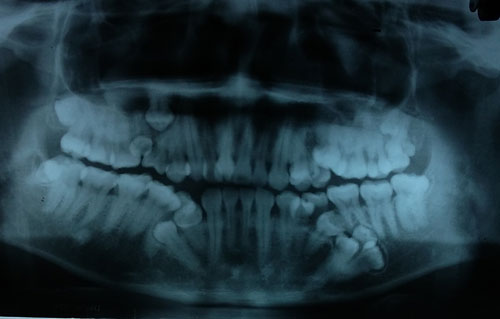

Bác sĩ khám răng cho một bệnh nhân. Bác sĩ tí thì ngất vì hàm răng của chàng thanh niên này. Làm gì chẳng đau khi hàm mọc thừa 13 chiếc và 4 chiến đang chiến để không thua kém chiêc khác.

Trong tuần này, các bác sĩ Bệnh viện Việt Nam - Cu Ba (Hà Nội) sẽ phẫu thuật tạo hình loại bỏ răng thừa cho bệnh nhân. Anh Văn Sơn 28 tuổi, cho biết từ năm học lớp 10 cứ mỗi năm lại thấy mọc thêm một chiếc răng, lúc hàm trên khi hàm dưới. Nghĩ là răng mọc lẫy, không thấy khó chịu hay vướng víu gì nên anh không đi khám răng. Lần khám gần đây nhất đã lâu, anh chỉ hàn răng bị sâu. Khi đó anh mới mọc 4 răng thừa, bác sĩ không tư vấn gì. Cách đây 10 ngày, đau nhức răng ở hàm trên bên trái không chịu được, anh Sơn đến Bệnh viện Việt Nam - Cu Ba khám. Bác sĩ bất ngờ khi phát hiện ngoài bị răng sâu, bệnh nhân còn mọc thừa đến 13 chiếc răng.

Bác sĩ Nguyễn Thị Thanh Châm, khoa Phẫu thuật Tạo hình Hàm mặt, Bệnh viện Việt Nam - Cu Ba cho biết, bệnh nhân mọc thừa đến 13 chiếc răng số 4 và 5 trên hai hàm - răng hàm nhỏ. Các răng mọc lệch, chen chúc, khó vệ sinh, cặn thức ăn dính vào kẽ lâu ngày tạo thành các mảng bám, một răng bị sâu viêm tủy khiến bệnh nhân đau nhức khó chịu.

"Bước đầu chúng tôi điều trị tủy dứt cơn đau răng. Bệnh nhân được chụp phim, làm xét nghiệm để chuẩn bị mổ bỏ các răng thừa", bác sĩ Trâm nói.

Bác sĩ Nguyễn Thanh Thái, Trưởng khoa Phẫu thuật Tạo hình Hàm mặt, cho biết thêm, ngoài 13 răng đã mọc thừa, kết quả chụp CT hàm dưới còn phát hiện thêm 4 mầm răng. Những răng này chưa mọc nên sẽ được theo dõi và xử lý sau.

Hàm dưới bệnh nhân còn 4 mầm răng chưa nhô lên. Ảnh: BSCC.

"Hiện tượng mọc thừa răng không phải chuyện lạ, tuy nhiên bình thường mỗi người chỉ mọc thừa 1-2; nhiều lắm thì 3 chiếc. Năm ngoái có bệnh nhân mọc thừa đến 8 chiếc, không ngờ anh Sơn còn nhiều răng thừa hơn", bác sĩ Thái nói.

Bác sĩ khuyến cáo, người dân nên rèn thói quen khám răng định kỳ 6 tháng một lần. Khi có hiện tượng răng mọc 2-3 cái một chỗ thì nên đi khám, bác sĩ sẽ tư vấn xem có cần thiết phải nhổ. Răng mọc thừa, khấp khểnh có thể làm xô lệch các răng khác, đồng thời lâu ngày thức ăn dắt vào các kẽ, vệ sinh răng miệng khó khiến răng bị sâu, viêm tủy, viêm lợi...